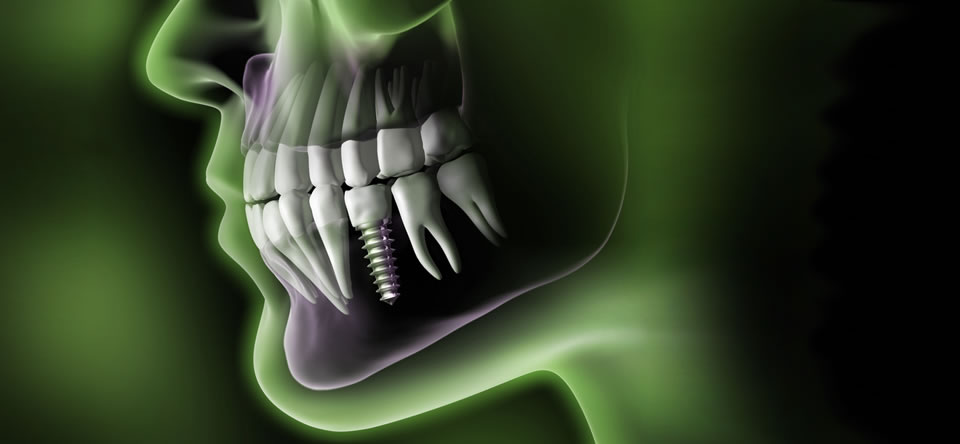

Top Service - unkomplizierte Wurzelbehandlung und Implantation. Professionelle Beratung.

Super nettes Team. Habe ein Frontzahnimplantat bekommen. Ich glaube es war schwierig, aber man sieht es nicht! Einfach perfekt. Ich kann diese Praxis nur empfehlen.

Ich habe 10 Implantate und Knochenaufbau bekommen. Das Team war extrem einfühlsam. Eine kompetente und zuverlässige Betreuung. Die Praxis ist auf dem neuesten Stand der Technik. Die Beratung und Durchführung der Arbeit war professionell. Besser geht's nicht - 1000 Dank!